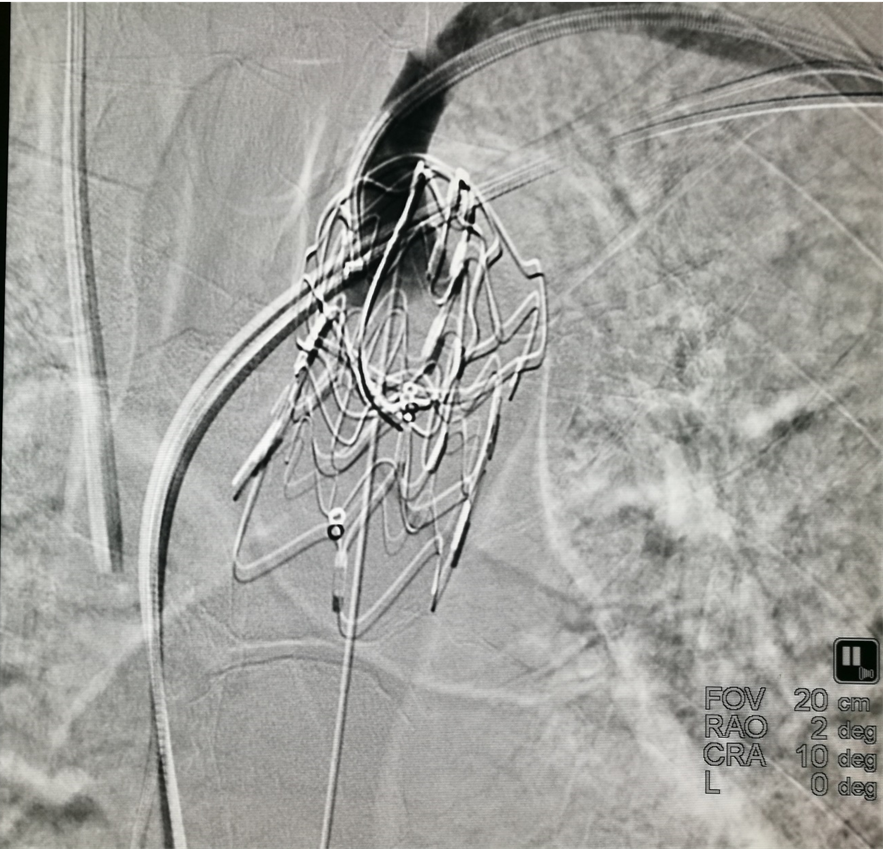

导丝破膜,各角度反复确认

机械破膜和激光破膜

破膜装置开窗

原位开窗存在问题:

分支角度和走行的扭曲;

器械贴壁行走,和血管轴线不重合(类似支架不对称释放),导致穿破风险;

激光开窗气泡问题,打断导管;

扩张后边缘不圆,裂口,漏。